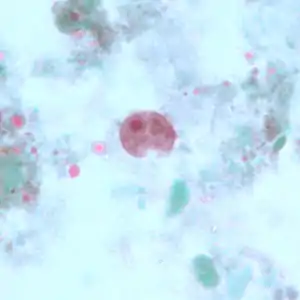

Cyst

The cysts are 8–10 micrometres in diameter, with a thick wall and a large glycogen vacuole that stains darkly with iodine. Usually harmless, it may cause amebiasis in immunologically compromised individuals.

[5][6] As the second form of I. butschlii, cysts have an oval shaped- single nucleus with a prominent nuclear endosome. This form is also large, single, glycogen-filled vacuole called iodinophilous vacuole (glycogen stains with iodine). Cysts are the infective stage of I. buetschlii. Unlike trophozoites, cysts are often found in formed stools.[4]